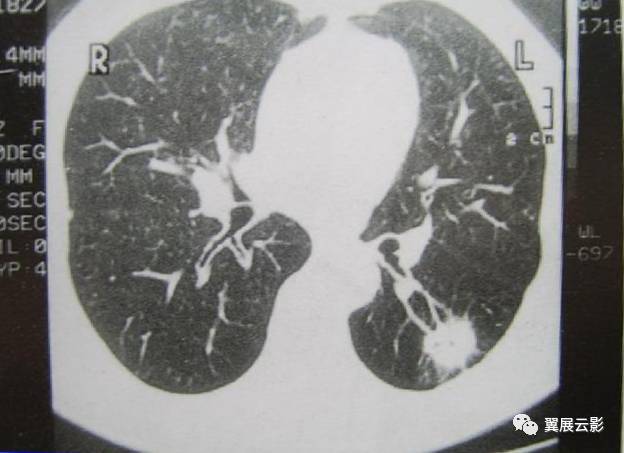

尘肺一期的ct图片,一期尘肺

尘肺的影像表现及鉴别诊断

一期尘肺

一期尘肺高清影像图片

一期尘肺图片 轻微

尘肺病ct影象图片

尘肺的ct图片

尘肺一期的ct图片早期

一期尘肺图片

早期尘肺胸片图 一期